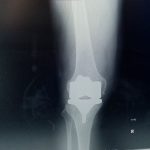

Zespół specjalistów z Oddziału Chirurgii Urazowo-Ortopedycznej szpitala w Brzesku przeprowadził kolejne nowe zabiegi z zakresu traumatologii narządu ruchu. Tym razem były to zabiegi endorptezoplastyki stawu kolanowego endoproteząprotezą ACS.

Jest to specjalna endoproteza dedykowana dla chorych z potwierdzonym uczuleniem na chrom oraz nikiel – wyjaśnia lekarz kierujący oddziałem, doktor Krzysztof Szklanny. Zwykłe endoprotezy stawu biodrowego i kolanowego standardowo zawierają te metale. U niewielkiego odsetka pacjentów, wykazujących uczulenie właśnie na nikiel i chrom, nie byłoby możliwości wykonania endoprotezy lub wiązałoby się z dużym ryzykiem reakcji alergicznej. To z kolei skutkować może stanem zapalnym, odrzuceniem oraz obluzowaniem endoprotezy. Wbrew pozorom, odsetek pacjentów z potwierdzonym uczuleniem nie jest tak mały, dodaje doktor Szklanny.

Dlatego, wychodząc naprzeciw potrzebom pacjentów, zespół ortopedów podjął się nowego wyzwania, wszczepiając kilku chorym z udokumentowanym uczuleniem, tak zwaną „złotą endoprotezę”. Swoją nazwę proteza zawdzięcza azotkowi tytanu (NiT), którym jest pokryta. To właśnie on nadaje jej złoty kolor. Tą samą substancję chemiczną, wykorzystuje się także w jubilerstwie i kosmetologii.